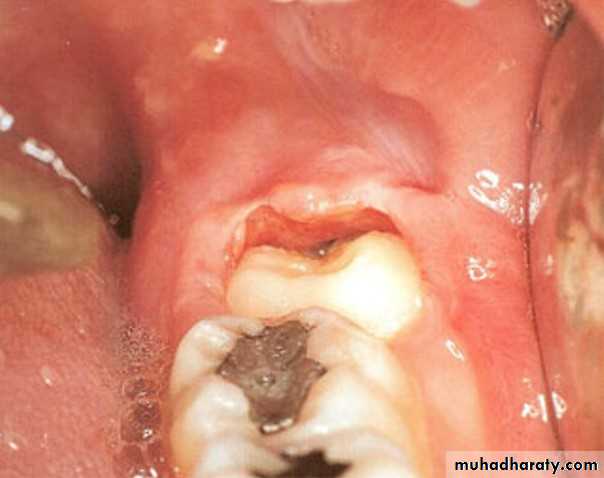

Periodontal abscesses are associated with poorly localized dull pain, adjacent teeth are tender, clenching the teeth, which are usually vital, characteristically brings relief. Mobility of teeth, pathologic sinuses, and evidence of periodontitis are often presentPericoronitis :

Pericoronitis produces rapid onset of soreness or pain in the soft tissues surrounding the crown of a partially irrupted tooth.In the case of impacted third molars particularly the lower ones this soreness is a associated with pain on swallowing and trismus these symptoms are particularly sever in cases of acute pericoronitis. Subacute pericoronitis Is also associated with soreness, pain on swallowing, and trims but their degree severity is milder than that of the acute phase of the disease.